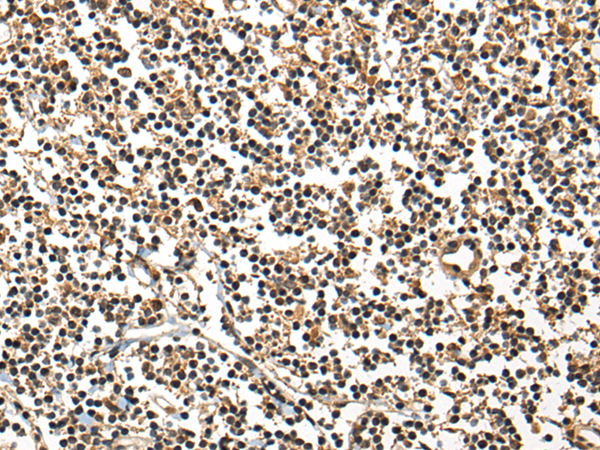

分类: 科研抗体货号: P09457别名: BL11; HB15应用: IHC反应种属: Human